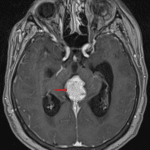

MRI

- Pineal region mass measuring 3.3 x 2.5 x 2.5 cm

- Diffuse intermediate T2 signal, restricted diffusion, and avid enhancement

- Peripheral foci of susceptibility artifact corresponding to calcification on the CT

- Downward mass effect on the tectum with obstructive hydrocephalus at the level of the cerebral aqueduct and subependymal edema